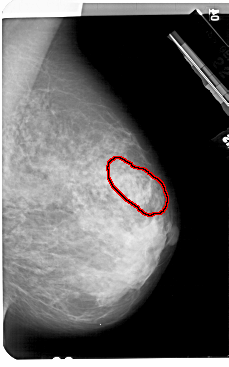

A_1504_1.LEFT_CC

LEFT_CC LINES 5491 PIXELS_PER_LINE 3586 BITS_PER_PIXEL 12 RESOLUTION 43.5 NON_OVERLAY

FILE: A_1504_1.RIGHT_CC.OVERLAY

TOTAL_ABNORMALITIES 1

ABNORMALITY 1

LESION_TYPE MASS SHAPE ARCHITECTURAL_DISTORTION MARGINS SPICULATED

ASSESSMENT 5

SUBTLETY 3

PATHOLOGY MALIGNANT

TOTAL_OUTLINES 1

BOUNDARY